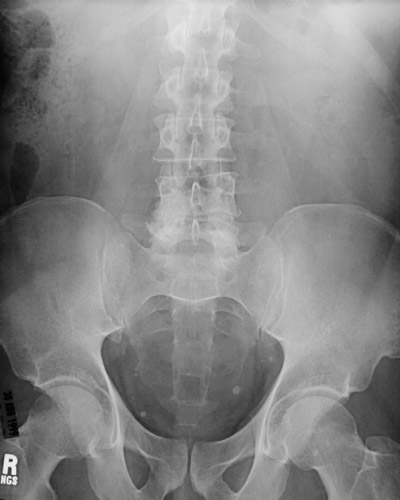

| This abdominal plain film reveals multiple small, discrete bright densities in the pelvis. These are phleboliths, or small calcifications that are a fairly common finding in middle-aged to older adults. Phleboliths have no significance, other than to distinguish them from other objects such as urinary tract calculi. A magnified view is seen below. |